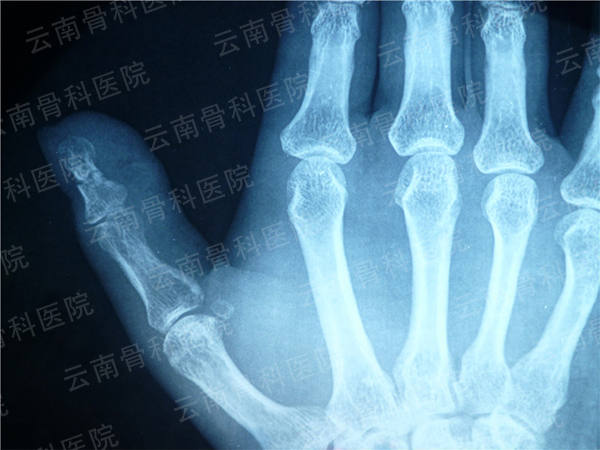

拇指Ⅲ度再造